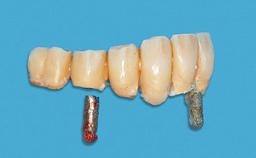

Improving an Existing Implant-supported Denture in an Alzheimer Patient with Bipolar Affective Disorder with Moderate Depression and Dementia

Prosthesis Type RDP

SAC Level Advanced

Defining Characteristics Fully edentulous lower jaw to be rehabilitated with an implant-borne removable overdenture